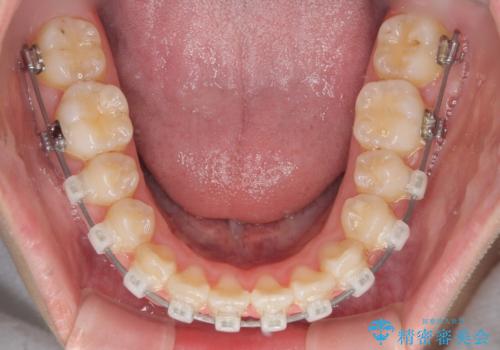

- 矯正装置

- クリアブラケット

- 中学生の頃にぶつけた前歯に不格好なクラウンが装着されており、出っ歯な印象になっていることを気にして来院された患者様です。

ぶつけてしまった歯は保存が困難な状況であったので抜歯をし、ワイヤー矯正により歯列を整えつつ前歯の突出感を解消することとしました。

矯正治療後にはインプラント補綴治療を行うこととしました。